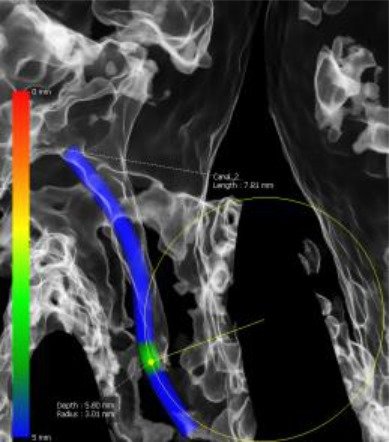

Das Green X ist ein 4-in-1 Röntgenbildgebungssystem der Superlative, welches sowohl 2D-Modalitäten wie Panorama- und kephalometrische Aufnahmen in ultrahochauflösender Bildqualität ermöglicht, als auch flexible 3D-DVT-Aufnahmen von Patienten, Modellen und Abformlöffeln.

Das Green X ist mit 49μm bei einem FOV von 4x4 cm das Gerät mit einem der weltweit höchsten Auflösungen und der daraus resultierenden Detailschärfe. Dank der byzzEz3D-i Software mit dem Endo-Modul rekonstruiert diese aus ultrahochauflösenden Schichtaufnahmen perfekte 3D Aufnahmen. Diese können dann als Hologramm in allen drei Dimensionen vermessen werden.

Ein ideales Instrument zur Vorbereitung für jede Wurzelkanalaufbereitung und WSR und auch ein hervorragendes Hilfsmittel zur 3D-Visualisierung, Behandlungsplanung und Patientenberatung.

Die byzzEz3D-i Software mit dem erweiterbaren Endo-Modul rekonstruiert aus den ultra-hochauflösenden Schichtaufnahmen perfekte 3D-Aufnahmen. Die 3D-Endo-Aufnahmen können als Hologramm in allen drei Dimensionen vermessen werden. Sowohl die Bi- und Trifurkation, Kanalanzahl, Kanalverlauf, Kanallänge und -durchmesser sowie die Krümmungsradien können einfach farblich gekennzeichnet werden. Damit ist das 3D-Endo-Modul nicht nur ein ideales Instrument zur Vorbereitung für die Wurzelkanalaufbereitung und WSR, sondern auch ein hervorragendes Hilfsmittel zur 3D-Visualisierung, Behandlungsplanung und Patientenberatung.

Green X von orangedental Endo Aufnahme